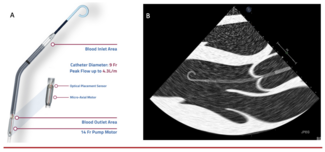

In this review, the authors discuss a brief history of the Impella mechanical circulatory support device, a mechanistic role for the device in the context of the underlying pathophysiology of acute myocardial infarction cardiogenic shock...